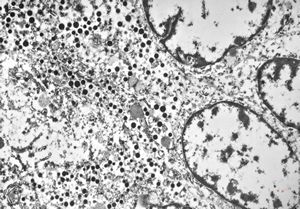

F,41y. | synovial metaplasia - capsule of implantate

F,41y. | synovial metaplasia - capsule of implantate

F,41y. | synovial metaplasia - capsule of implantate

F,41y. | synovial metaplasia - capsule of implantate

F,41y. | synovial metaplasia - capsule of implantate

F,41y. | synovial metaplasia - capsule of implantate

F,41y. | synovial metaplasia - capsule of implantate

F,41y. | synovial metaplasia - capsule of implantate

F,41y. | synovial metaplasia - capsule of implantate